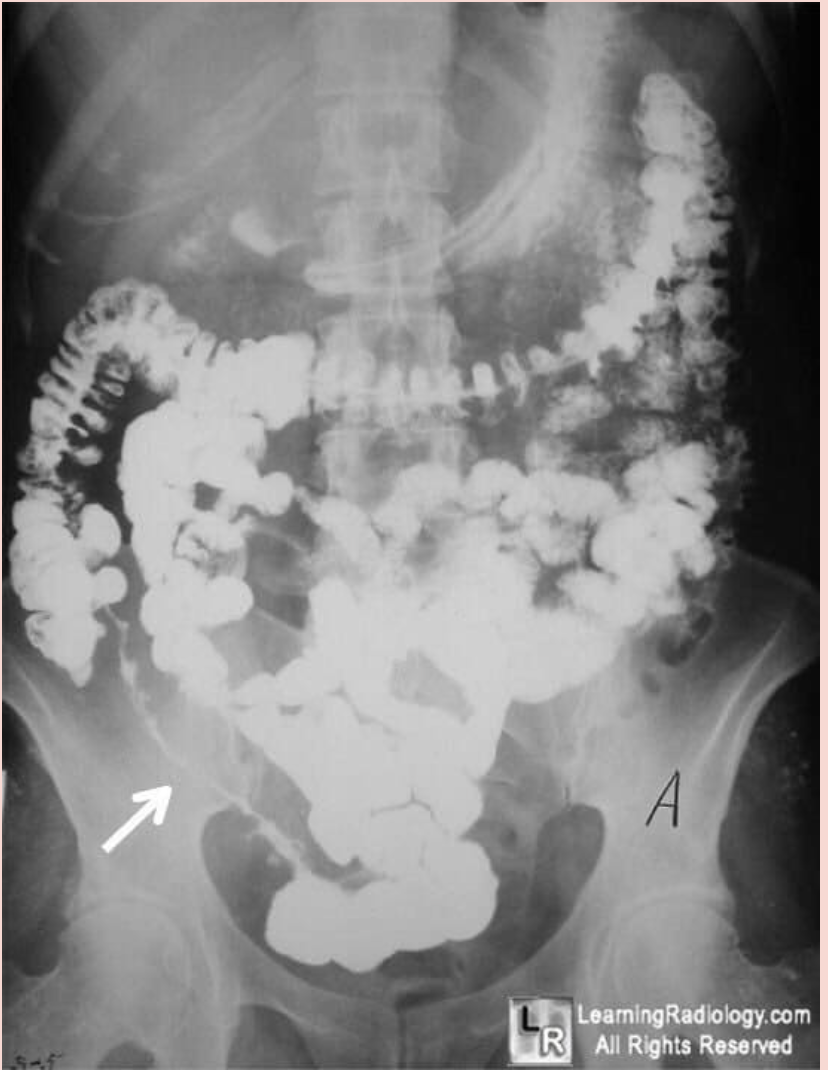

What pathology causes the following presentation (shown by the white arrow)?

Answer: Crohn’s disease

Explanation: Known as ‘string sign’, this observation is classically found in Crohn’s disease. It occurs in both stenotic and non-stenotic phases of the disease; in non-stenotic regions, it is of variable width and is secondary to oedema and GI spasm. In stenotic regions, the diameter is fixed secondary to the scarring and fibrosis seen in severe Crohn’s disease presentations.